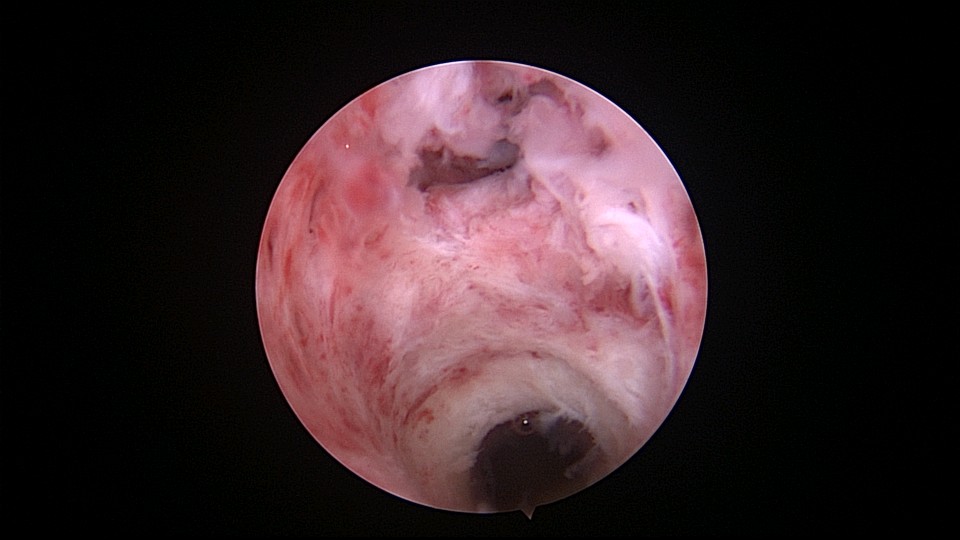

患者56岁,G2P1,剖宫产1次。安环30年,绝经7年,外院取环失败,形成假道。子宫后倾后屈位,宫颈外口萎缩狭小,宫颈管扩张膨大,宫颈管左前壁假道,宫颈内口狭窄坚硬,宫腔镜见宫腔偏向右后方,并向左后侧屈,镜子艰难进入宫腔,O型环位置正常,异物钳取出,宫腔无其他异常。